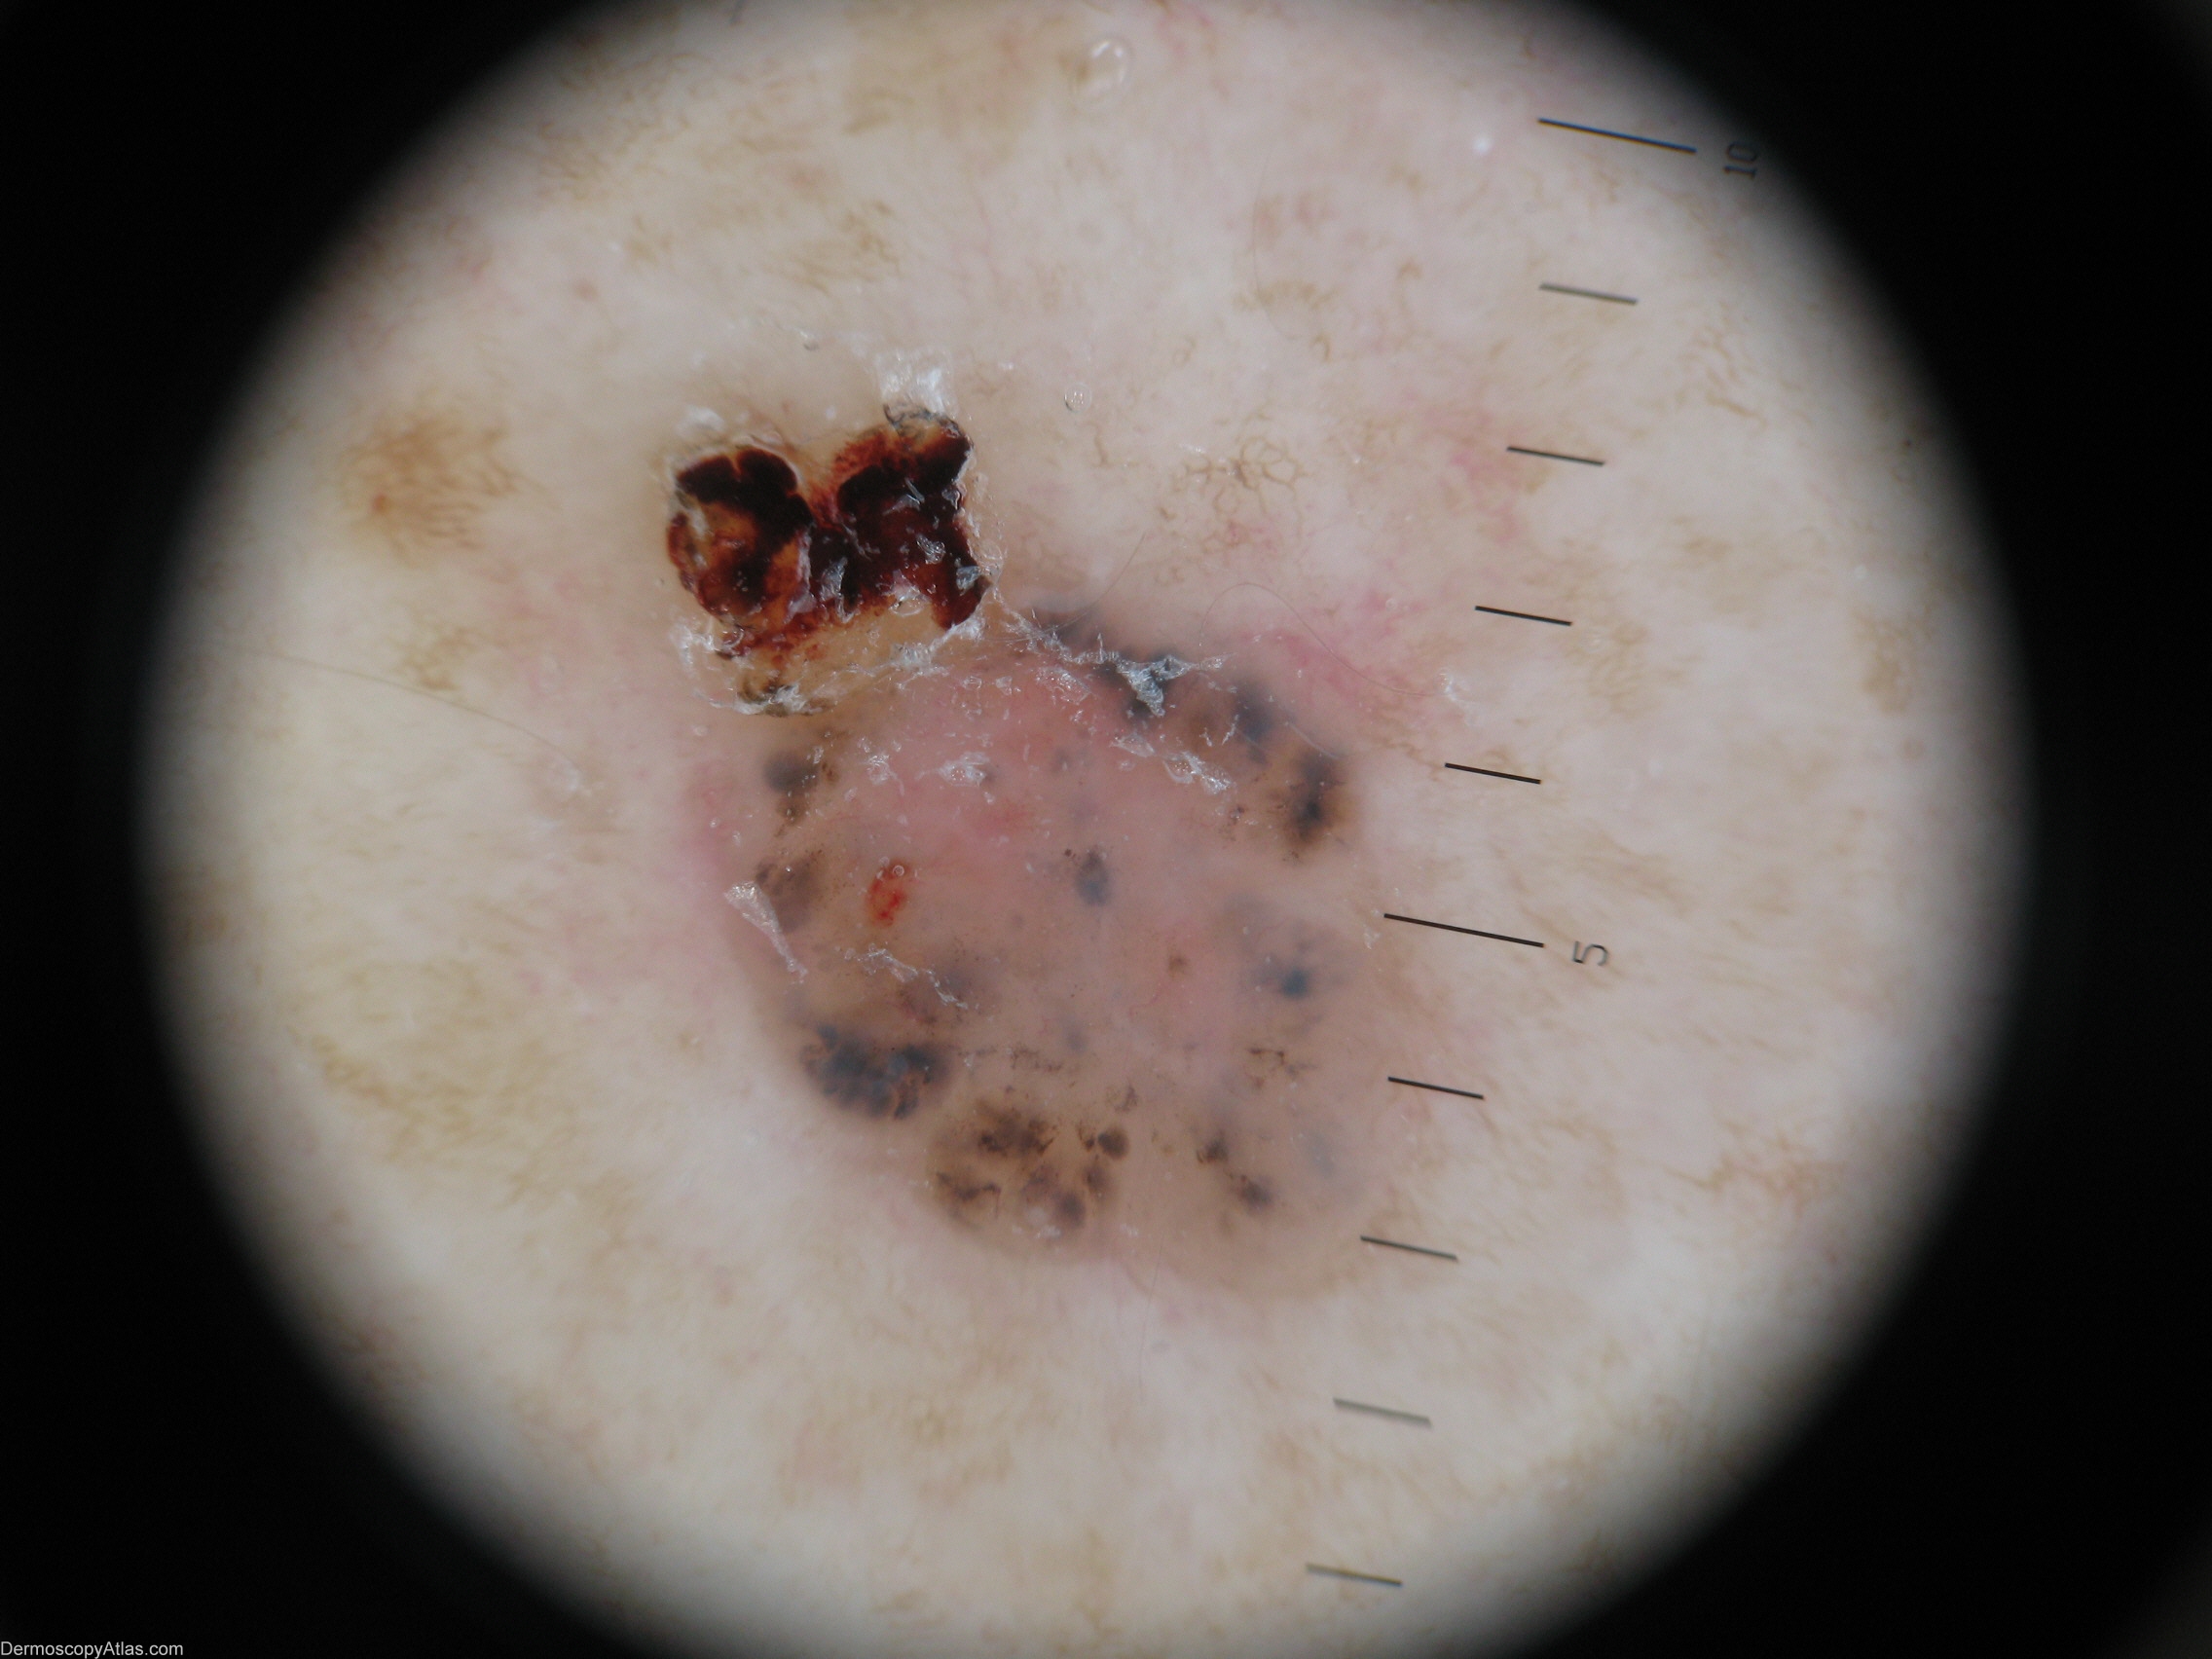

Description: Macro view

This elderly lady was unaware of this lesion on her back.

It shows classical features of a pigmented BCC with Blue ovoid nests/Blue clods.

It has few vessels but has a dishwater colour often seen in a BCC. It has some ulceration.

A good example of a Maple leaf like structure is seen at 7 o'clock.